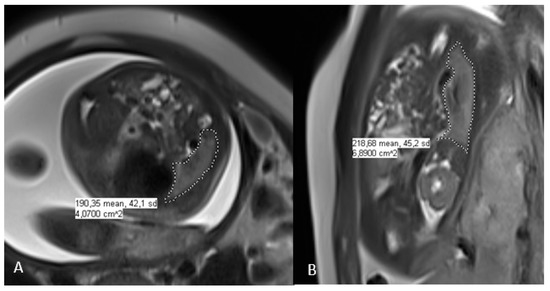

2.4. Fetal Lung Volume Measurement on MRI